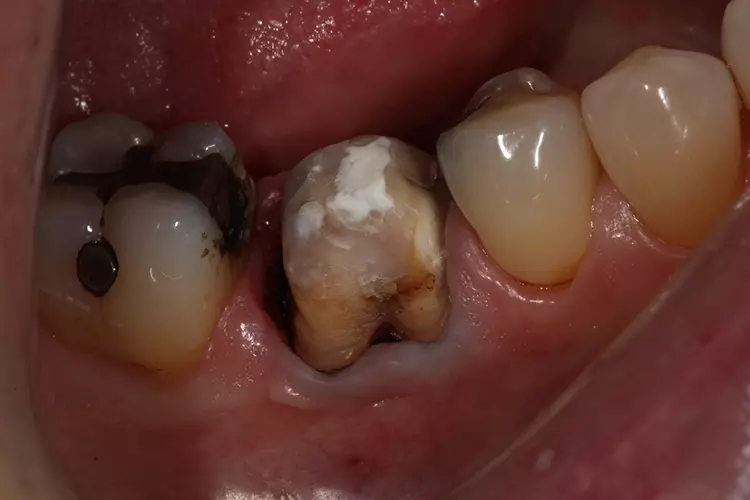

Die klinische Untersuchung zeigte eine klobige Metallkeramikkrone auf Zahn 46. Der Parodontale Screening Index ergab einen Wert von 3 im unteren rechten Sextanten.

Beim Sondieren traten Blutungen auf, die distal von Zahn 46 stärker ausgeprägt waren. Daher wurde an dieser Stelle ein weiteres 6-Punkt-Taschendiagramm erstellt, das Taschen von 4 mm Tiefe auf der distobukkalen Seite von Zahn 46 mit Blutungen zeigte. Zusätzliche Perkussionstests im unteren rechten Quadranten ließen erkennen, dass Zahn 46 nicht auf Perkussion reagierte.

Die Behandlung begann mit dem Auftrennen und der Entfernung der Krone. Anschließend wurde die Sekundärkaries entfernt und der Stumpf mit VisCalor bulk (VOCO) repariert. Hierbei handelt es sich um ein Bulk-Fill-Komposit mit thermisch kontrollierter Viskosität, welches sich gut für Klasse-II-Restaurationen oder Stumpfrekonstruktionen eignet.

Die Krone wurde mit einem konischen Diamantschleifer mit flachem Kopf (Frank Dental) aufgetrennt. Kariöses Gewebe wurde mit einem zylindrischen Diamantbohrer (835.010C, NTI) und einem Rosenbohrer (1204025RA, Edenta) entfernt.